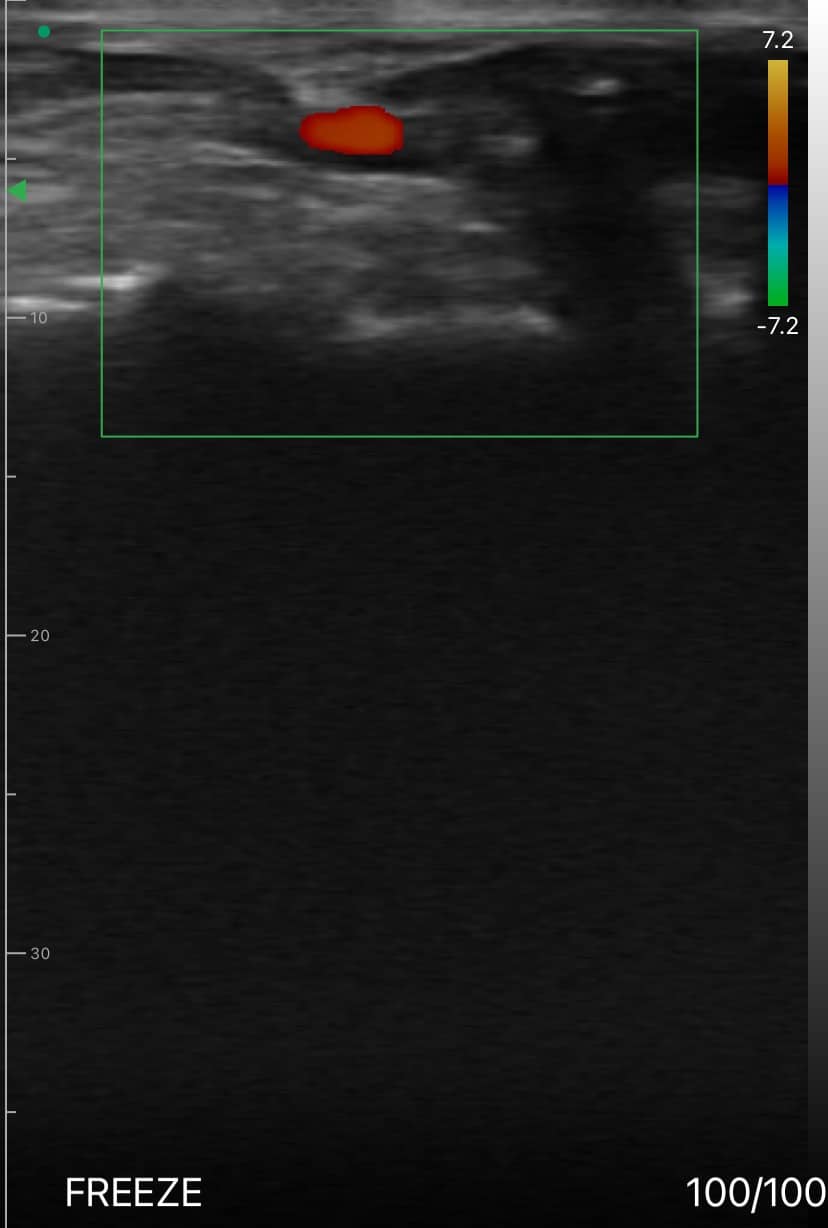

Artère dorsale du pied CDFI

Artère